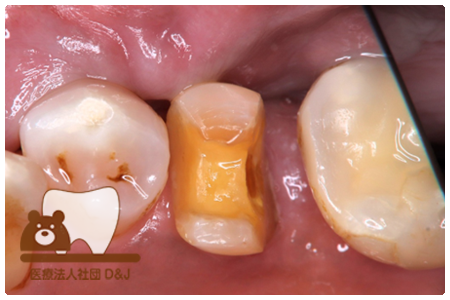

症例3フリジルコニアクラウン 左上6

治療前

治療後

59歳 男性

- 治療内容

- 虫歯で大きく失われた歯に対して、土台としてファイバーコアを使用し、その上にフルジルコニア製の被せ物を装着しました。見た目と強度を両立した自由診療の治療です。

- 治療期間

- 根の治療含めて3カ月半

- 費用

- 自費

フリジルコニアクラウン:77,000円(税込)

(R8.2月時点)

- その他の治療の費用は含まれておりません。

- リスク・副作用

- 強い力が加わると割れる可能性があります。また、噛み合わせや歯ぎしりの影響で脱離することがあります。